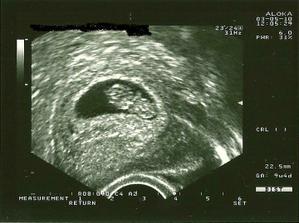

_3.5. 2010 - prvá návšteva u dr., srdiečko krásne bije, utz ukazuje 9tt + 4; 22mm 🙂